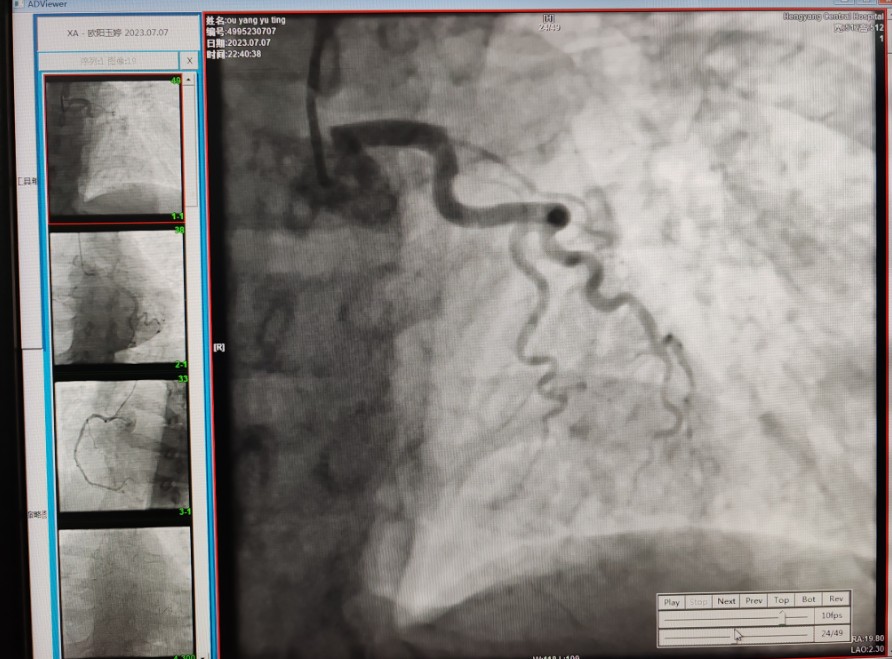

22:29分患者經(jīng)院內綠色通道送達導管室,手術由雷剛副主任醫(yī)師主刀,楊繼賀副主任醫(yī)師為第一助手,介入技師及護士密切配合,聞訊而來的趙慶禧主任醫(yī)師坐鎮(zhèn)協(xié)調指揮。22:37分手術開始,冠脈造影顯示心臟上最重要的一條冠狀動脈-前降支開口齊頭閉塞,血管粗大且血栓高負荷,非??简灲槿胄g者的手術能力,一旦發(fā)生冠脈無復流或操作不慎血栓帶入回旋支導致循環(huán)崩潰,病人幾乎無生還希望;此時,患者手術臺上仍持續(xù)胸痛,且血氧飽和度在高流量吸氧狀態(tài)下不到80%,雷剛副主任醫(yī)師一方面指揮鎮(zhèn)靜鎮(zhèn)痛及抗心衰治療,一方面緊急啟用IABP(主動脈球囊反搏),然后精細操控細如發(fā)絲的介入導絲迅速通過病變,并予冠脈球囊擴張、冠脈內溶栓、抗痙攣藥物使用、植入冠脈支架,最終成功開通“罪犯”血管,且無手術并發(fā)癥發(fā)生,整個過程張弛有度、快慢結合、一氣呵成?;颊咝g后胸痛明顯好轉,血氧飽和度上升至96%,術后1天轉出監(jiān)護病房,第3天拔出IABP,目前已康復出院。